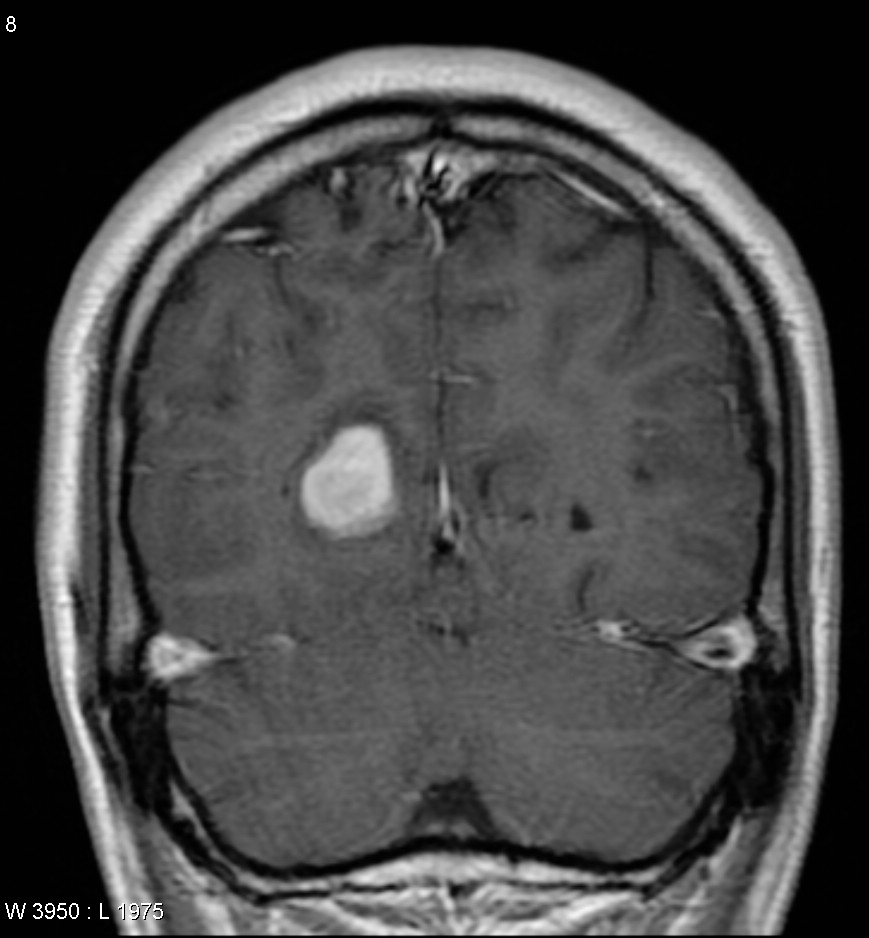

МРТ головного мозга: показания и результаты

Раздел: Визуальный дайджест